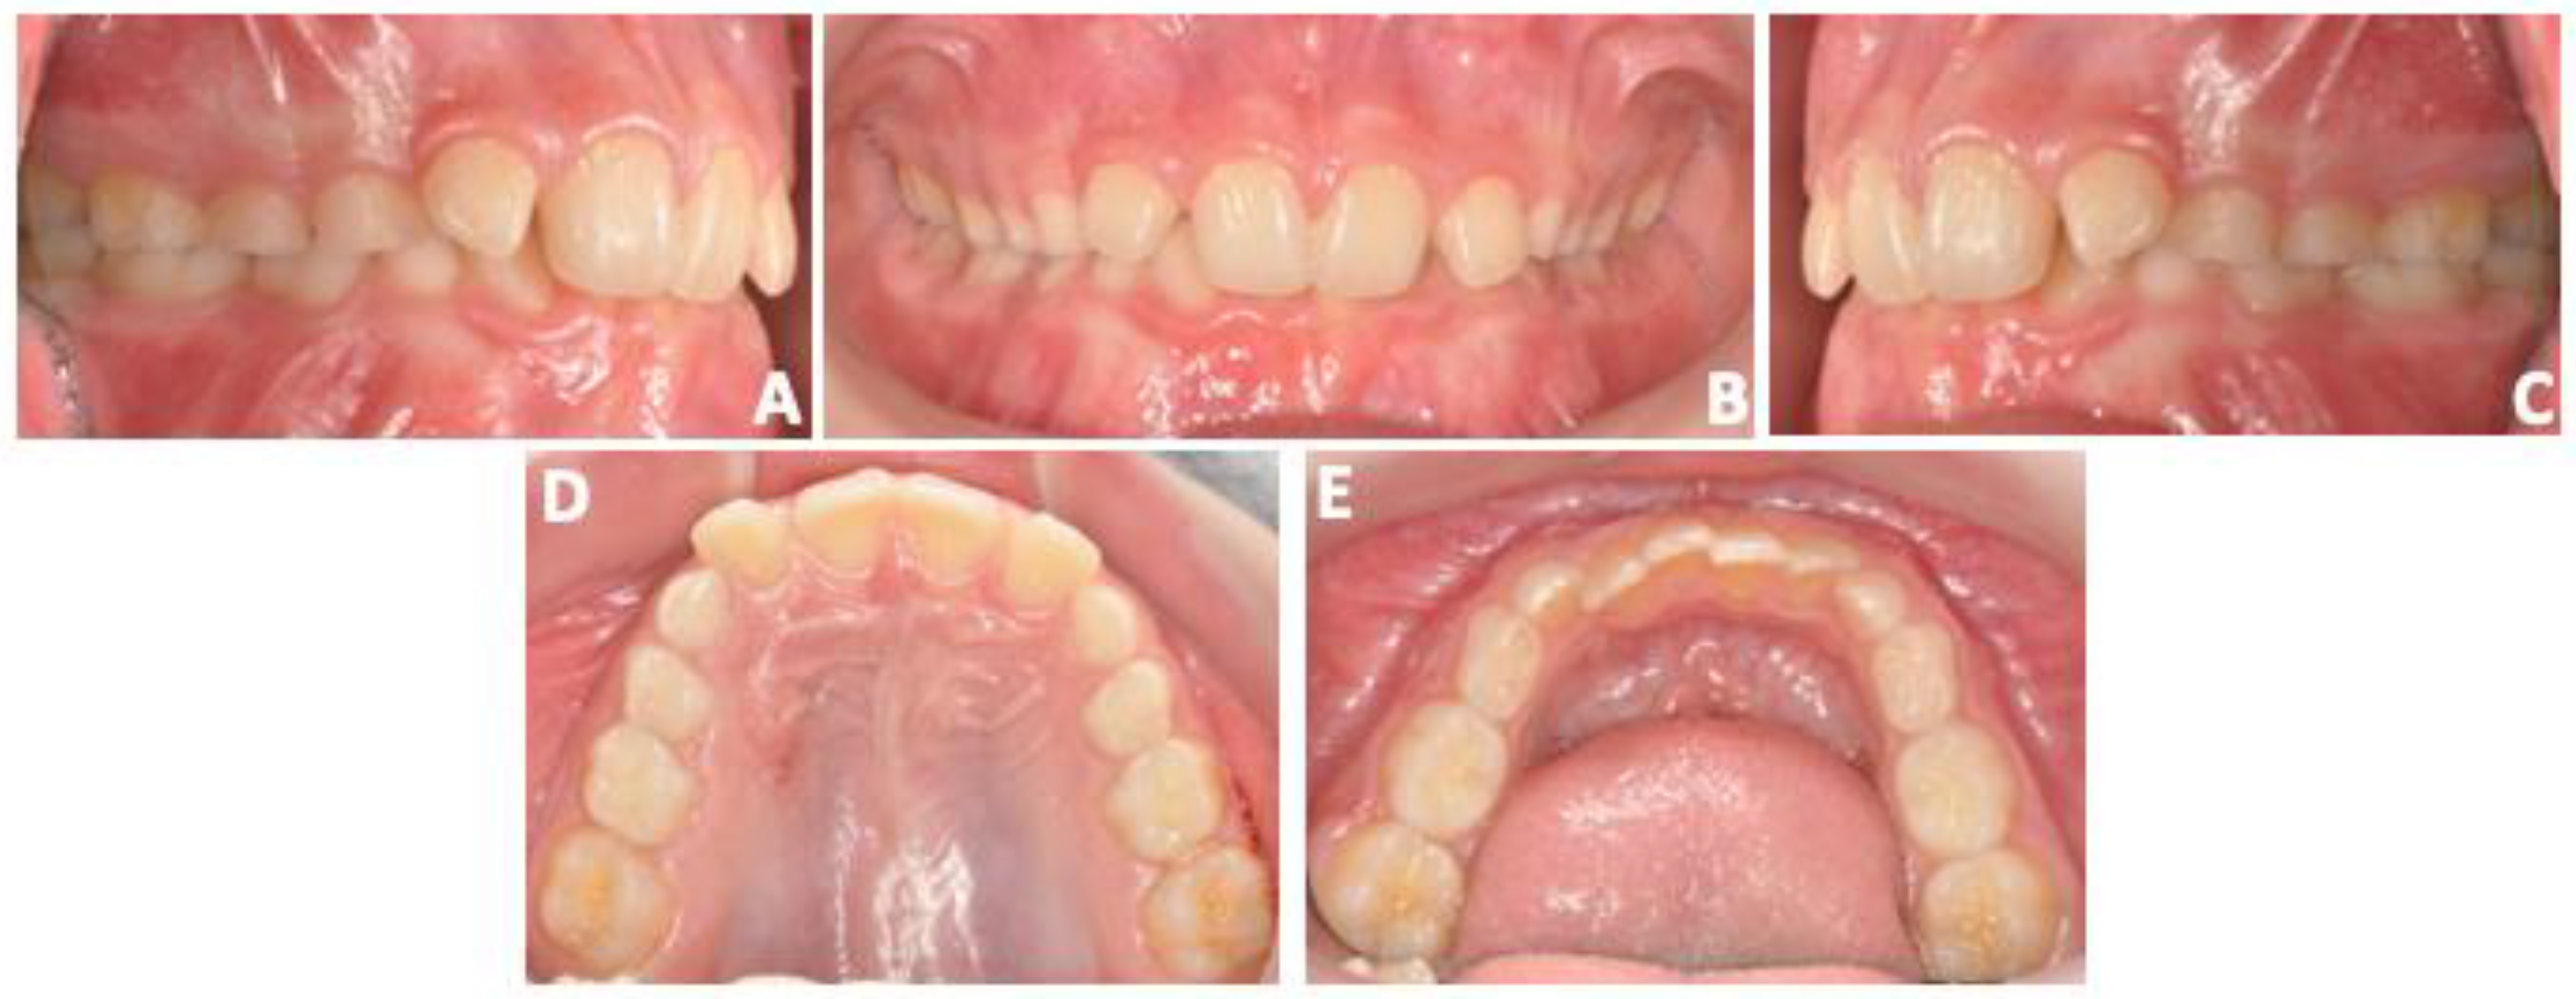

Figure 2.

Pre-treatment intra-oral examination. (A–C) Point of view (POV) of occlusion, (D) upper arch, (E) lower arch.

Cephalometric analysis revealed a skeletal class III discrepancy (ANB = −1.4^) with increased mandibular body length (Go-Gn = 70.2 mm), severe negative value of facial convexity angle (Na-Apo^ = −6.4^), hyperdivergent mandibular vertical growth pattern (MP-SN = 31.9^), and significant retro-inclination of the lower incisors (IMPA^ = 80) (Figure 3A,B). Comparing intra-oral and cephalometric data, there was a remarkable inconsistency between dental malocclusion (Class II) and skeletal sagittal discrepancy (Class III) that could be attributed to the dental compensation of the malocclusion. The panoramic radiograph revealed a normal stage of tooth eruption and an absence of inflammatory conditions (Figure 4).

Twelve months after treatment, the patient underwent an orthodontic diagnostic check-up to verify treatment progress. As expected, the patient maintained baseline facial characteristics related to the facial growth pattern (Figure 8A–C). The patient maintained the same slight Class II molar and canine dental relationship in mixed dentition. In general, intra-oral examination revealed a similar occlusal condition compared to the baseline except for the retro-inclination of the lower incisors (Figure 9A–E). Cephalometric analysis confirmed a significant improvement in skeletal parameters. In particular, the patient presented a normal sagittal skeletal relationship (ANB^ = 1.8) with a significant improvement in the facial convexity angle (Na-Apo^ = −0.6) and a hyperdivergent mandibular vertical growth pattern (MP-SN = 31.6^); however, there was a significant retro-inclination of the lower incisors (IMPA^ = 76.1) that should be interpreted as the consequence of the application of distal forces generated in the anterior mandibular region (Figure 10A,B). At this stage, the patient was asked to reduce wearing time and to wear the appliance only at night.

Figure 9.

Post-treatment intra-oral examination. (A–C) Point of view (POV) of occlusion, (D) upper arch, (E) lower arch.